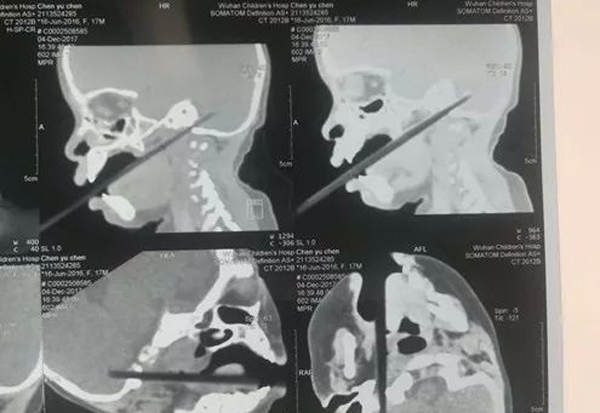

Terkejut dan panik melihat keadaan mangsa, ibu bapanya terus membawanya ke hospital. Setelah menjalani CT Scan, mangsa terus dibedah segara untuk mengeluarkan objek tersebut.

Ketika pembedahan itu berlangsung, doktor mendapati 2 sentimeter dari chopstick itu telah menembusi otak mangsa. Mujur objek itu tidak menembusi otak mangsa terlalu dalam dan mangsa dirawat di Unit Rawatan Rapi untuk kerana berisiko terkena jangkitan.